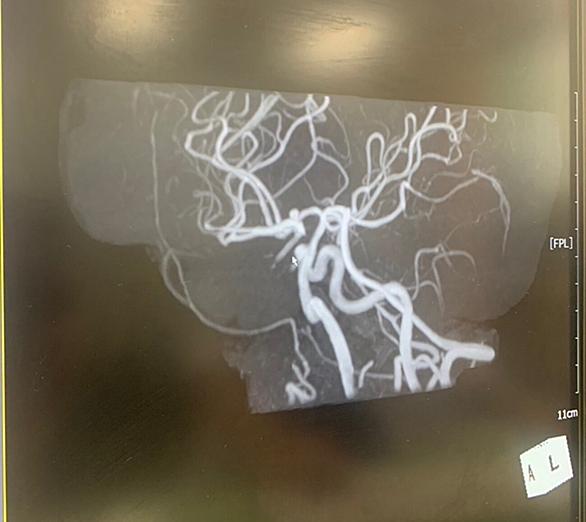

今回は、「未破裂脳動脈瘤」についてお送りします。 未破裂脳動脈瘤は、早期に発見して対応することが大切です。 皆様の参考になれば幸いです。 <未破裂脳動脈瘤とは> 脳の動脈のある部分がコブ状に膨らんだ状態を脳動脈瘤といいます。 未破裂脳動脈瘤とは、脳動脈にできたコブが破裂しないままの状態であることをいいます。 この脳動脈瘤が破裂すると、脳を包んでいる「クモ膜」という膜の内側に出血を起こします。これがクモ膜下出血です。 <脳動脈瘤ができやすい場所> 動脈瘤は、一般的には血管の枝分かれした部分にできます。 血流に押される形で徐々に風船のように大きくなると考えられています。 この袋が大きくなればなるほ…